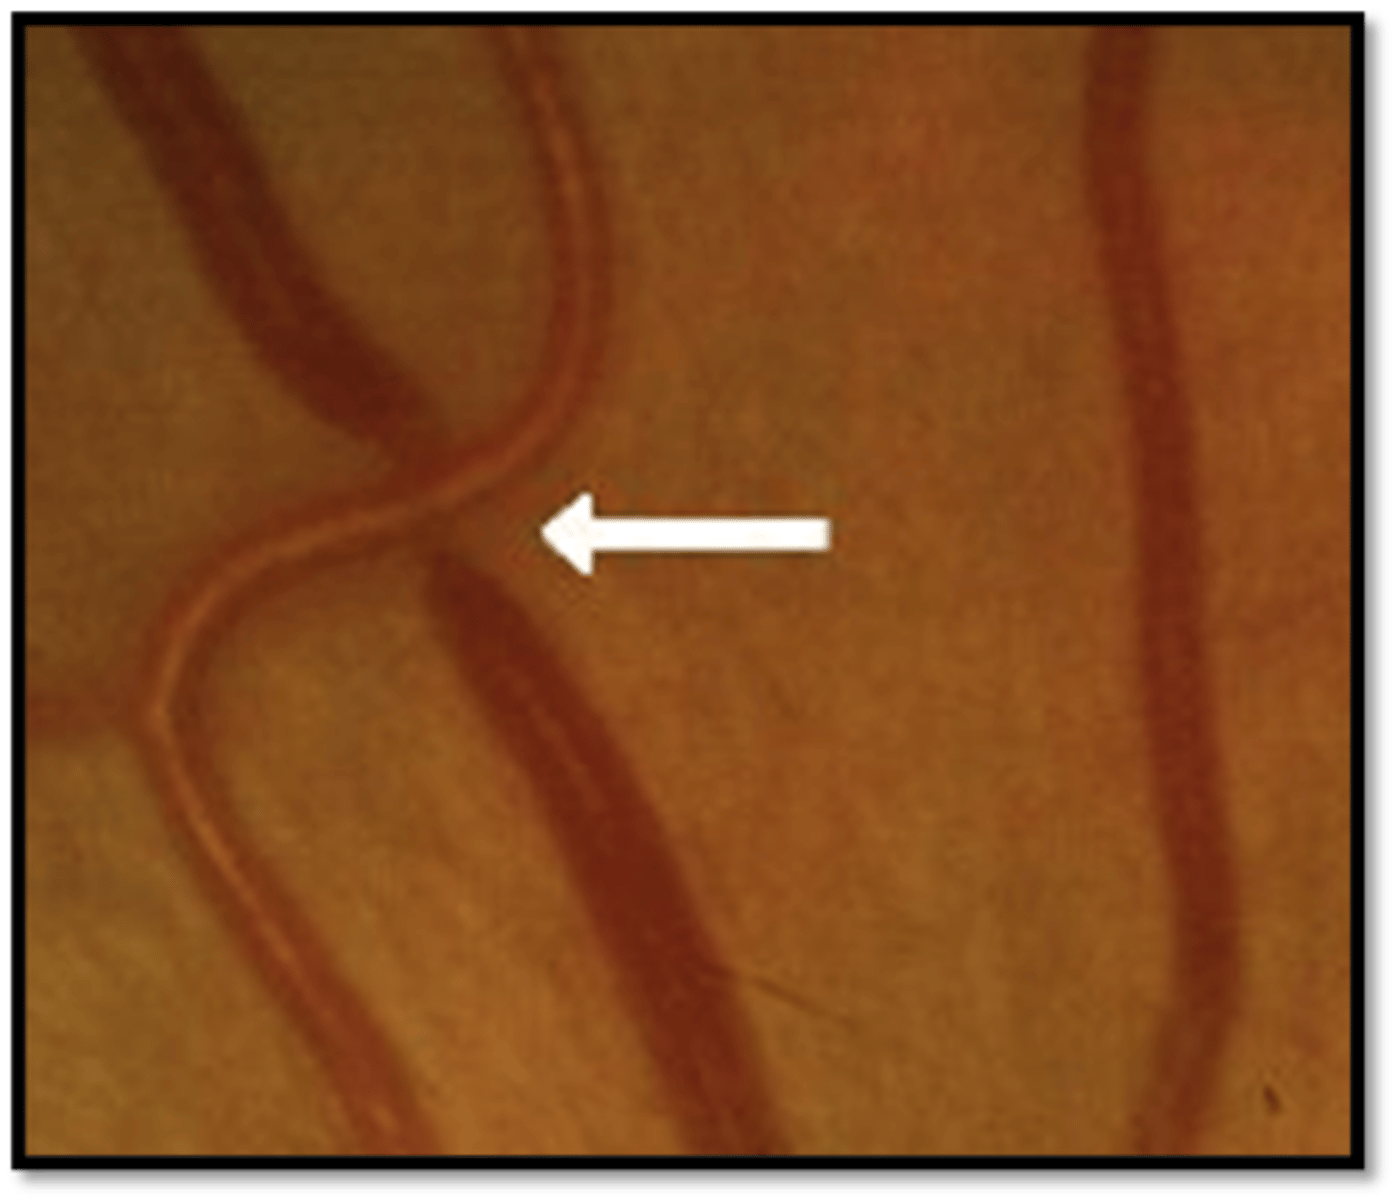

AV Nicking & Banking - Grade 2 appearance

-Occurs at AV crossings

-Most common in superior temporal arcade

-Compression of the retinal vein at their common sheath causes venous nicking/banking, dilation, and tortuosity